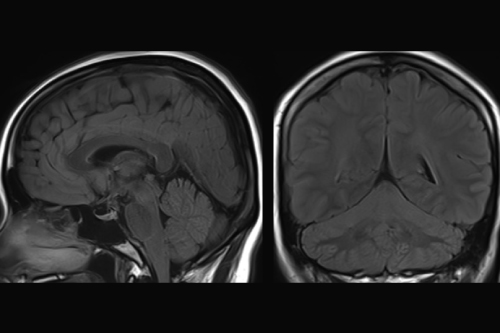

キアリ奇形

咳やいきみで誘発される咳嗽性頭痛の約40%は頭の中の病気があるともいわれています。咳嗽性頭痛の代表例がキアリ奇形です。小脳が下方に下垂しており、時に脊髄空洞症を伴います。